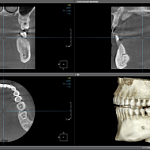

Современная диагностика: КТ с визуализацией всех суставов и пазух теперь в "Самсоне"

Больше области - больше информации: КТ 15×10 в "Самсоне" против стандартных аппаратов